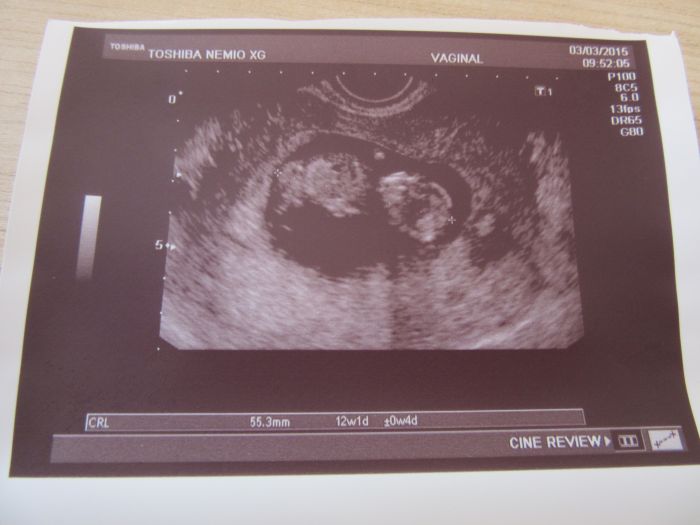

Ahoj holky, tak to dneska klaplo, jsem šťastná. Screening dopadl dobře, vše je v naprostém pořádku a za 14 dní se dozvím jak dopadla krev, pokud se jim něco nebude líbit tak se ozvou. Jinak mně vše ukázal i jak mám plný nacpaný žaludeček, to jsem teda koukala, nebude to zatím žádný divoch,jen trošičku se tam hýbal, ale moc tomu nedal. Jsem dnes 12+1 a měříme 5,53cm. Přikládám fotečky.